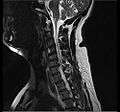

MRI scan of cervical disc herniation between fifth and sixth cervical vertebral bodies. Note that herniation between sixth and seventh cervical vertebral bodies is most common.

MRI scan of cervical disc herniation between sixth and seventh cervical vertebral bodies.